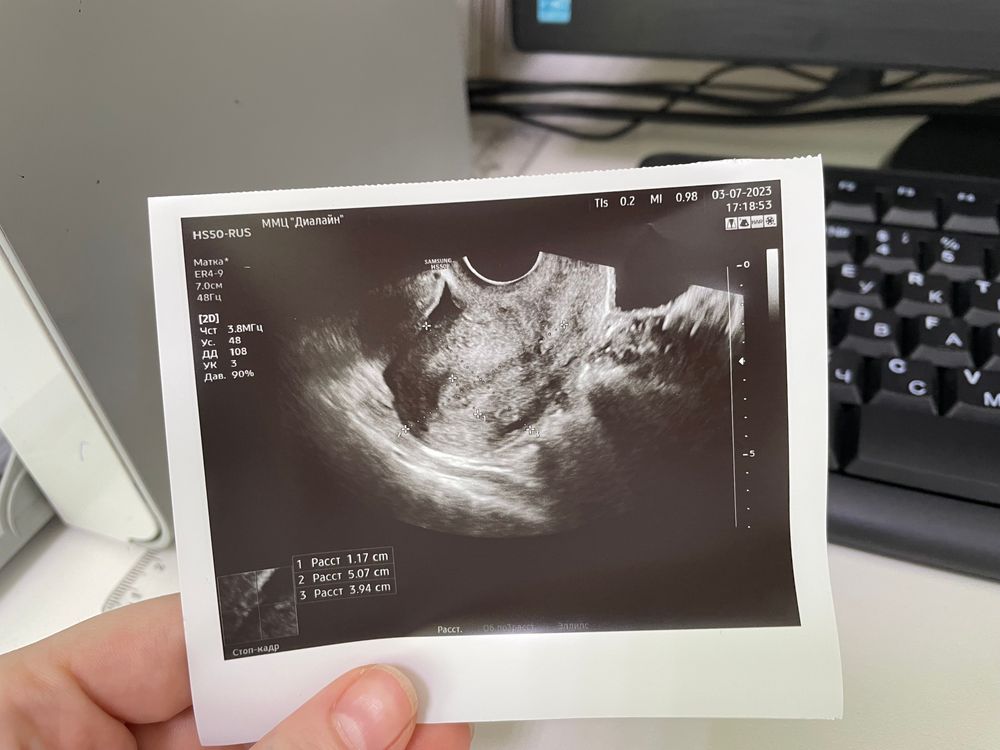

Фолликулометриясходила на узи, впервые вырос эндометрий 12мм!! 14дц, я просто в шоке. у меня максимум был 8-9 и то на 20+дц (у меня долгие нестабильные циклы по 38-40+дней) ДФ 21мм 😃🙏🏻 через неделю на контроль овуляции.

03.07.2023